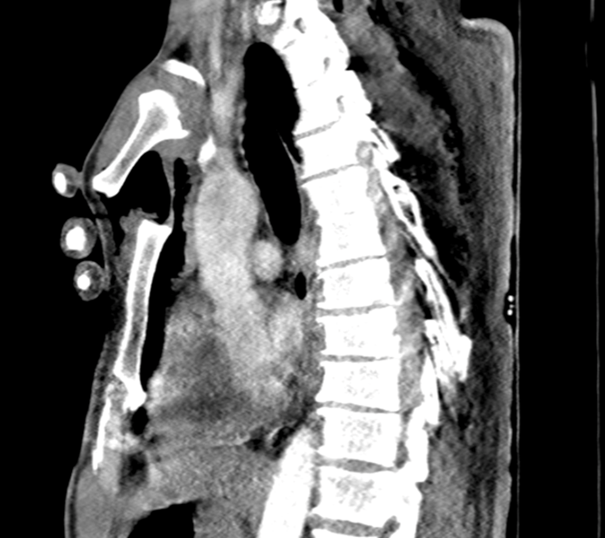

On physical examination, the manubrium sterni appeared anteriorly displaced. Palpation revealed pain, sternal instability, and subcutaneous crepitus. Routine biochemical investigations were unremarkable. Thoracic computed tomography (CT) revealed bilateral multiple rib fractures, bilateral hemopneumothorax, subcutaneous emphysema (Figure 1), and a fracture at the angulus sterni resulting in separation between the manubrium and the corpus sterni (Figure 2).

Figure 1 Axial thoracic CT image demonstrating trauma-induced bilateral hemopneumothorax, multiple rib fractures, and subcutaneous emphysema.